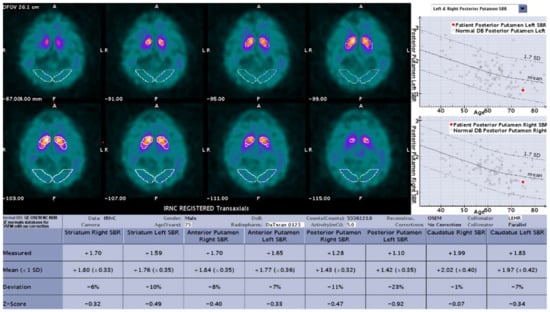

DaT-SPECT images from all three study groups were evaluated using DaTQUANTTM software, which reconstructed all SPECT data with the same reconstruction algorithm and filter parameters as those used for the normal database and performed a volume-of-interest (VOI) determination of radiotracer binding in different regions of the striatum bilaterally. An area in the occipital cortex served as the background region. The quantified regions include striatum, caudate, putamen, anterior putamen, and posterior putamen. For each region, the striatal binding ratio (SBR: difference in mean counts between the region and background divided by the mean background counts), percent deviation from the age-matched mean of the normal database, z-score, and the age-matched mean value from the normal database is presented. Age-matching to the normal database is done on a year-by-year basis. The normal data base includes 118 healthy volunteers (no diagnosis of PS or first-degree blood relative with PS), including 73 men and 45 women, aged 31 to 84 years, who contributed to PPMI. Additional calculated values which are not background-corrected include putamen to caudate ratio (P:C), striatum asymmetry, caudate asymmetry, and putamen asymmetry (Figure 1).

Figure 1.

Sample result of the DaTQUANT software with the SBR (mean and deviation), z-scores, and percent deviation for multiple variables.